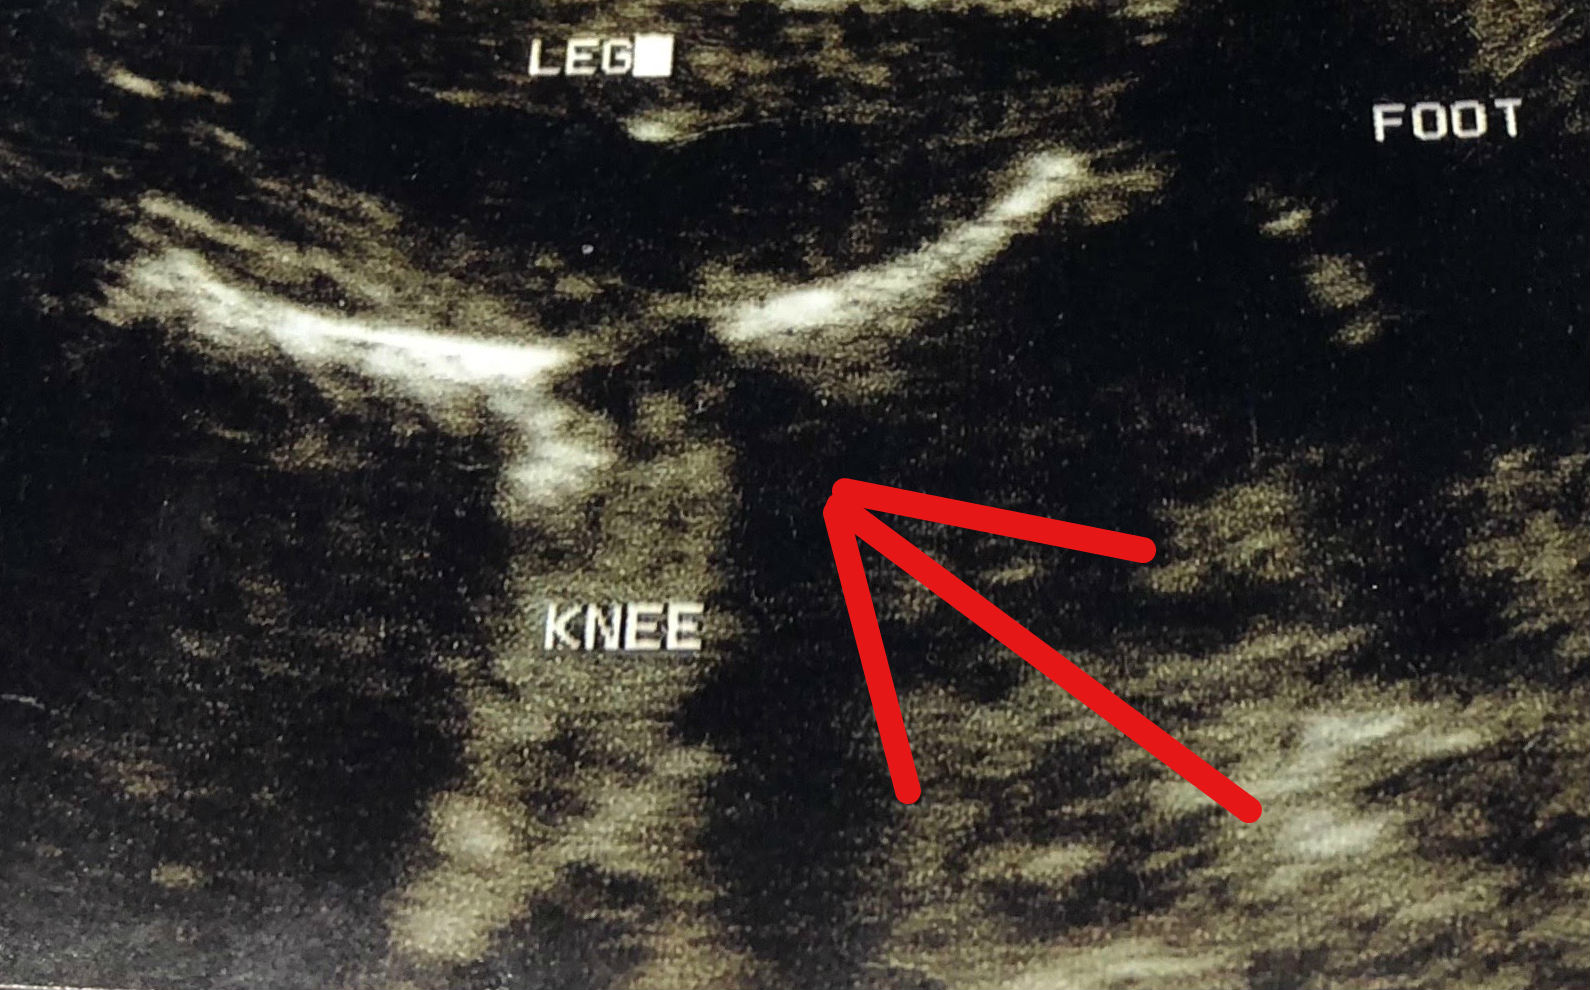

Here’s a close-up of the image: